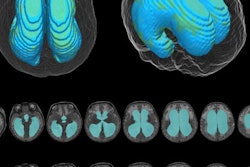

People with spontaneous intracranial hypotension are typically evaluated using CT myelography. But CT imparts radiation, and researchers have been exploring whether MRI myelography could offer a noninvasive alternative. Tay's team compared the diagnostic accuracy of CT myelography to MRI myelography for identifying CSF leaks in patients with spontaneous intracranial hypotension.

The study included 576 patients who underwent MR myelography and CT myelography exams. Of these, 276 (47.9%) were diagnosed with CSF leaks on both CT and MR myelography.